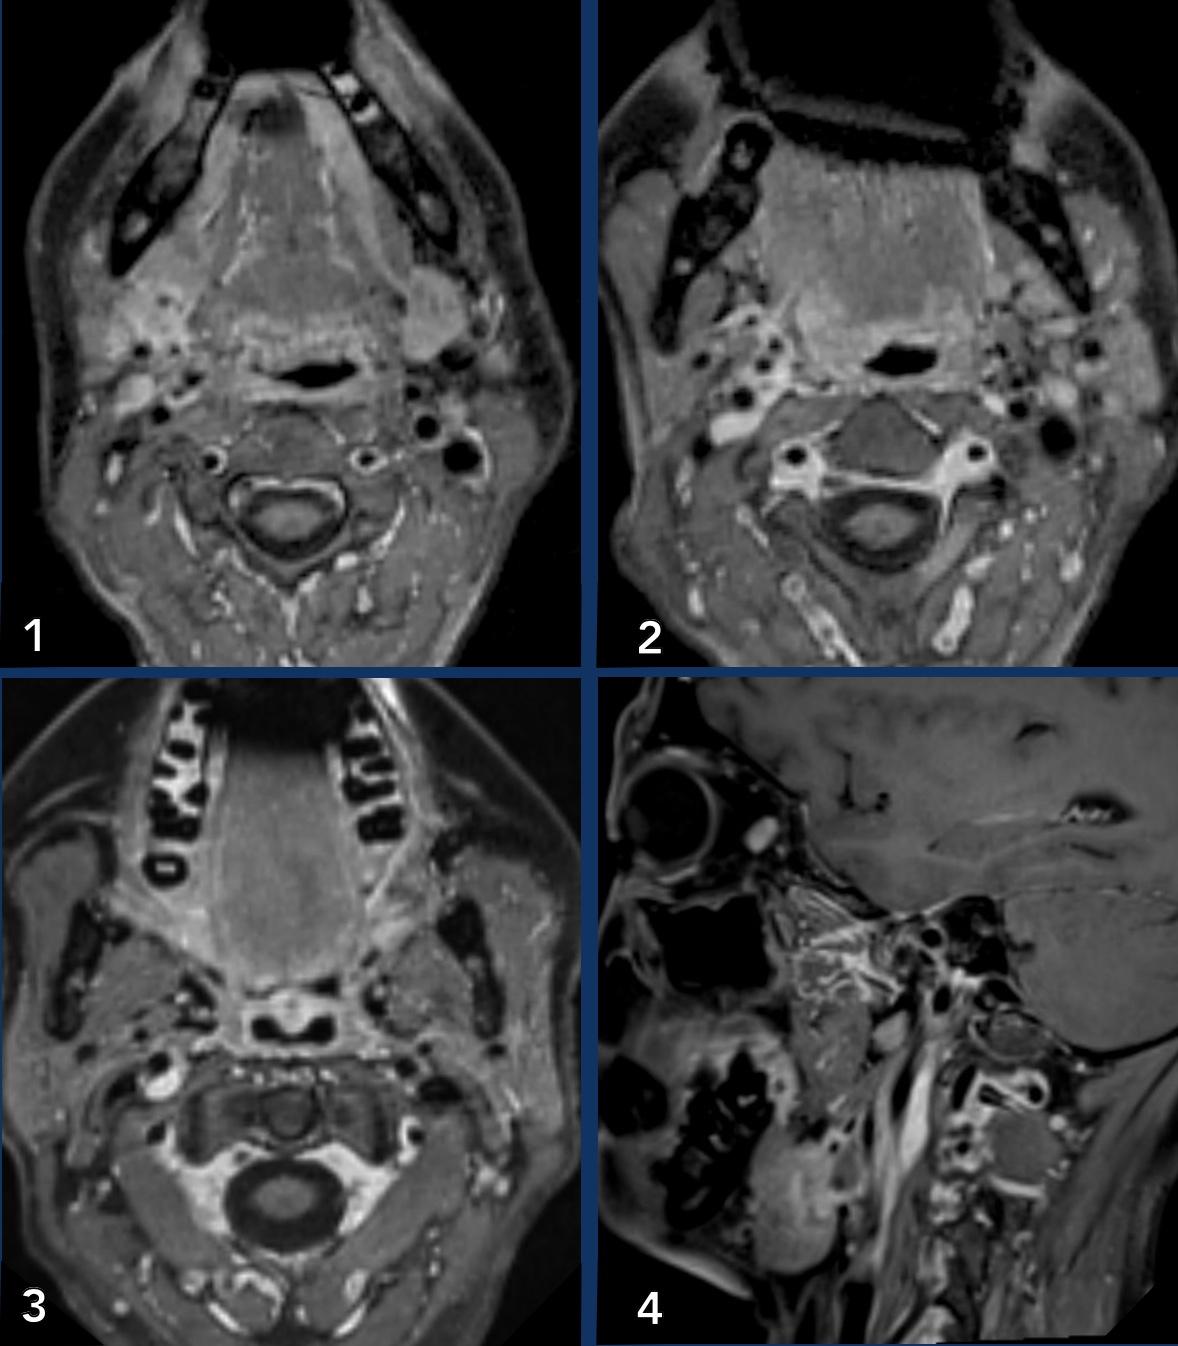

Carotid artery

Ca bệnh

Những

hình ảnh này của một bệnh nhân có khối sưng ở cổ trong vài năm.

Các nghiên cứu hình ảnh học chuyên sâu đã được thực hiện, nhưng tất cả các kết quả đều âm tính.

Bệnh nhân

hiện xuất hiện hội chứng Horner bên phải.

Study the images.

What are the findings?

Images

- Khi bạn so sánh tuyến dưới hàm phải và trái (hình 1), bạn

sẽ nhận thấy một tổn thương khối ngấm thuốc ở bên phải (mũi tên trên hình cuộn). - Sự tăng quang có thể được theo dõi trên hình 2 và 3 dọc theo động mạch cảnh trong và động mạch cảnh ngoài

- Điều này cũng có thể được nhận thấy trên hình ảnh mặt phẳng đứng dọc, nơi tuyến phì đại được nhìn thấy (*) và các vệt tăng quang dọc theo động mạch cảnh trong (đầu mũi tên).

Hình ảnh

Bảy tháng sau, khối u bao quanh động mạch cảnh trong (ICA) và động mạch cảnh ngoài (ECA) đã to hơn.

Kết luận

Đây là ung thư biểu mô tuyến dạng nang với sự lan rộng khối u theo đường thần kinh.